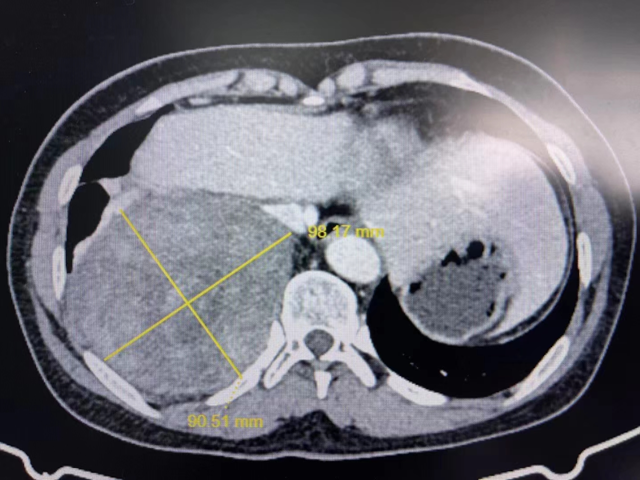

近日,刘女士因“头晕”在当地医院住院治疗,通过胸部增强CT检查发现,右侧肺底肿块已增大至约10cmX8.2cm大小,当地医生建议及时到上级医院进一步诊治。

手术中发现肿瘤大小约13cm*13cm*12cm,紧贴脊柱右侧,与右肺下叶、胸壁严重粘连,稍不注意就可能引发大出血,手术操作难度极大。